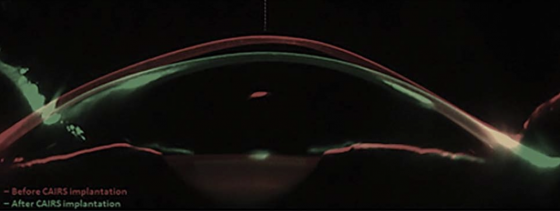

Corneal Allogenic Intrastromal Ring Segments (CAIRS) are stromal implants derived from donor corneal tissue used in the treatment of corneal ectasias, including keratoconus. CAIRS belongs to a broader family of corneal addition techniques aimed at flattening the cone and regularizing corneal shape, including synthetic intrastromal corneal ring segments (ICRS) and Corneal Tissue Addition Keratoplasty (CTAK). Unlike ICRS, which are made of rigid synthetic polymers, CAIRS offers a biocompatible alternative that integrates more naturally with host tissue.[1] While CTAK involves implanting gamma-irradiated donor segments that are customized to individual topography, processed by CorneaGen, and implanted exclusively with a femtosecond laser[2], CAIRS segments can be prepared and implanted manually or with femtosecond guidance. As an emerging technique, CAIRS currently encompasses a variety of surgical approaches, contributing to its adaptability across different clinical settings.

CAIRS implantation has consistently demonstrated improvement in both refractive and topographic parameters. According to a systematic review by Levy et al. (2025)[12], mean uncorrected distance visual acuity (UDVA) improved from 0.83 ± 0.15 to 0.40 ± 0.08 logMAR, and corrected distance visual acuity (CDVA) improved from 0.52 ± 0.22 to 0.19 ± 0.09 logMAR (p = 0.01 for both). Spherical equivalent (SE) decreased from −7.09 D to −2.34 D, while Kmax and Kmean were reduced from 57.8 ± 1.09 D to 53.57 ± 2.66 D and 49.27 ± 0.28 D to 45.30 ± 1.46 D, respectively.